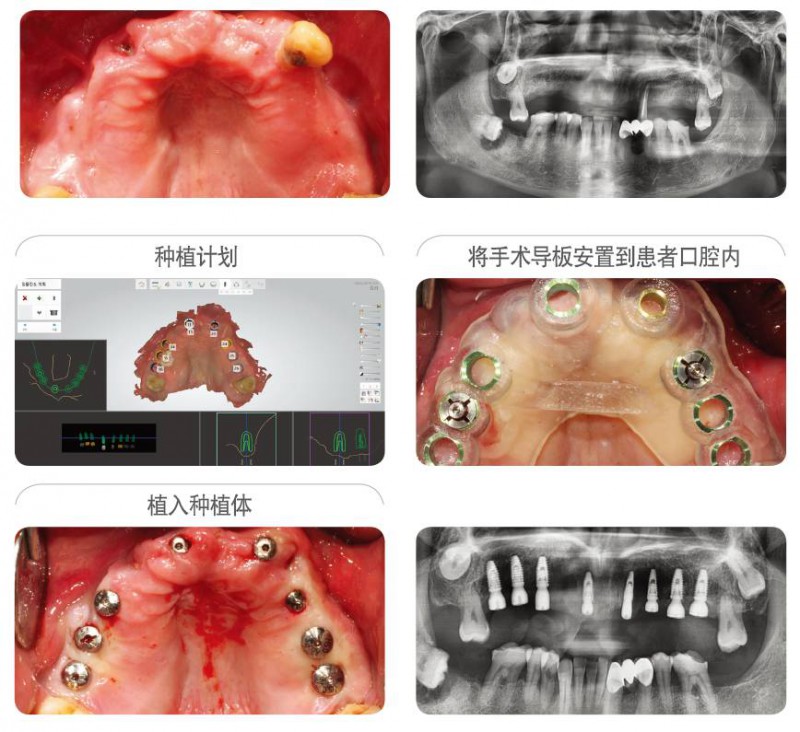

病例信息 : ST 牙科診所, 60s男性患者.

首次開(kāi)展種植的牙科醫(yī)生為自己家人施術(shù)的案例.利用紐白特?cái)?shù)字化手術(shù)導(dǎo)板簡(jiǎn)單的植入8顆種植體,使得在顧問(wèn)醫(yī)生的幫助下制定的治療計(jì)劃,完美的再現(xiàn)在患者口腔內(nèi)。